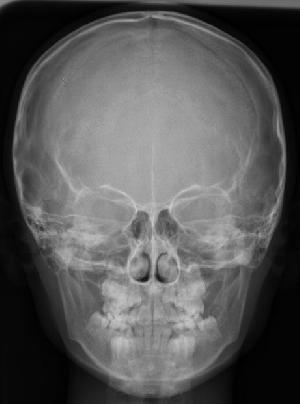

現在の歯の状況を把握するために、レントゲンや、顔・口の中の写真、歯の型をとります。

診査の結果をもとに、現状と治療計画・治療費などについて説明します。矯正でもっとも大切なのが診断です。骨格、歯の大きさなどすべてを審査してもっとも適切な治療を選択します。